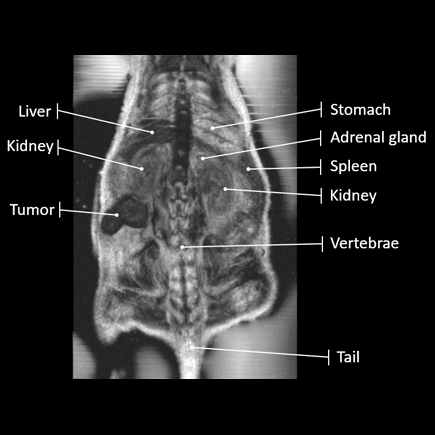

- Zautomatyzowane pozycjonowanie przetworników pozwala na skanować czołowe, strzałkowe i osiowe płaszczyzn ortogonalnych całego ciała, generując obrazy 3D o wysokiej rozdzielczości, które bardziej przypominają obrazy MRI niż tradycyjne USG.

Vega® to bezobsługowy, zautomatyzowany, wysokoprzepustowy, przedkliniczny system obrazowania ultrasonograficznego, który umożliwia obrazowanie ultrasonograficzne 2D i 3D o wysokiej rozdzielczości w zaledwie kilka minut. Ten innowacyjny system ultrasonograficzny in vivo eliminuje problemy wynikające z używania ręcznych głowic sonograficznych w modelach konwencjonalnych, dzięki zastosowaniu zautomatyzowanych przetworników umieszczonych pod stolikiem do obrazowania. Aparat Vega® jest łatwy w użyciu, wymaga minimalnego szkolenia i zapewnia standaryzację wyników.